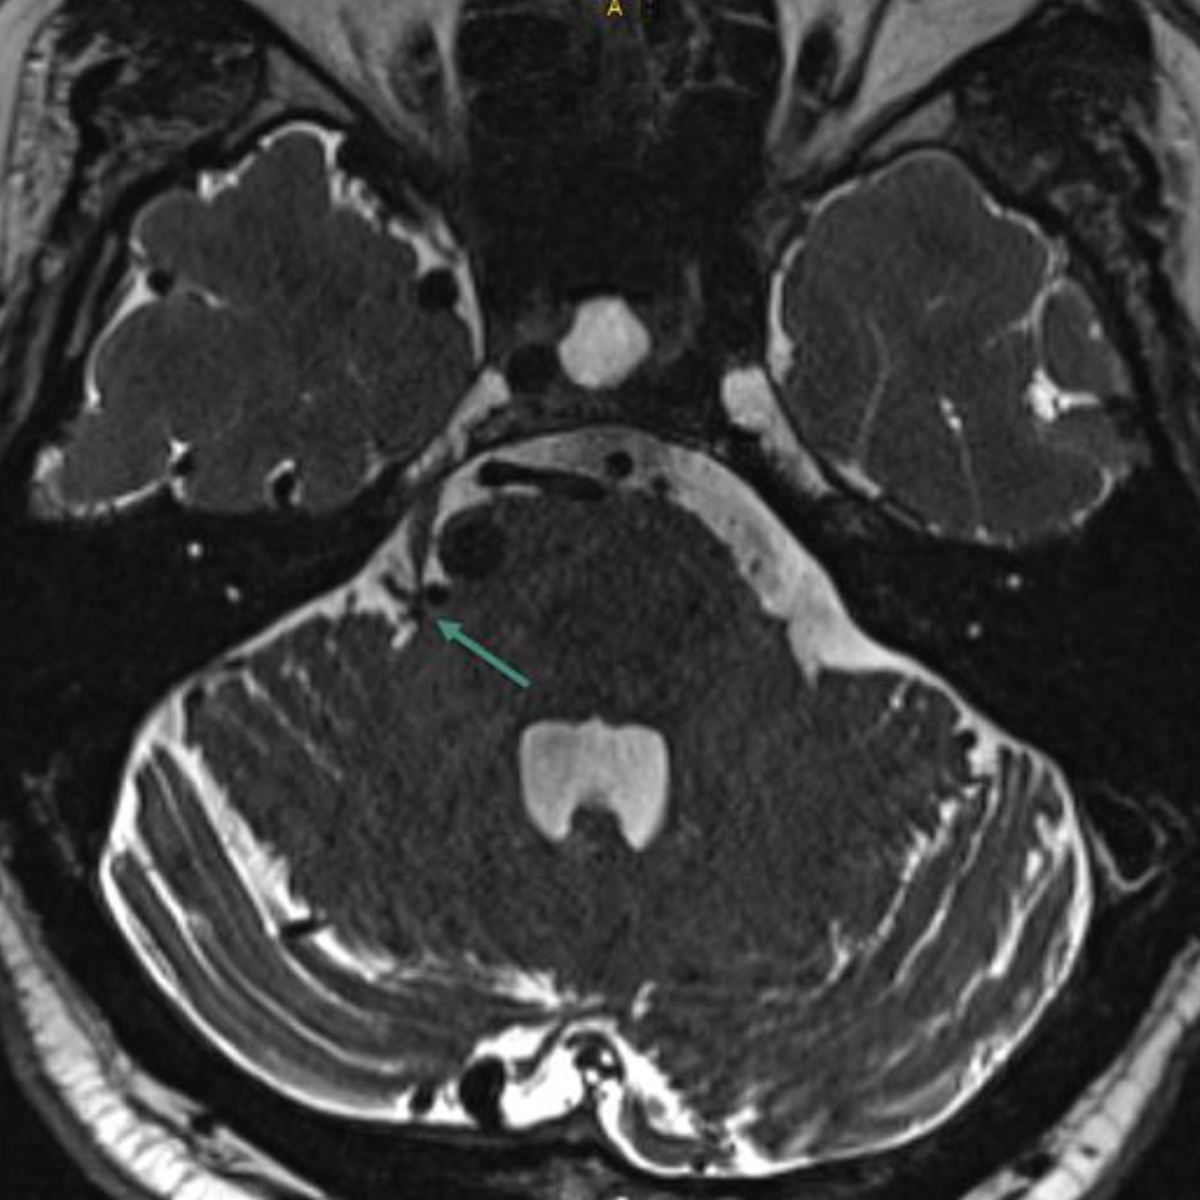

Every patient with suspected trigeminal neuralgia requires imaging to distinguish between classic trigeminal neuralgia and secondary causes. The current gold standard is magnetic resonance imaging (MRI), including high-resolution constructive interference in steady-state (CISS) sequences to exclude neurovascular compression, T2 sequences to detect possible inflammatory processes and angiography [9, 10] (figures 2, 3, 4). When assessing a possible pathological neurovascular contact, it is important (for planning potential surgical procedures) to distinguish between nerve displacement and atrophy [12].

Figure 4MRI showing pathological neurovascular contact of the right trigeminal nerve at the root entry zone due to a dilated vein associated with an arteriovenous malformation (green arrow).